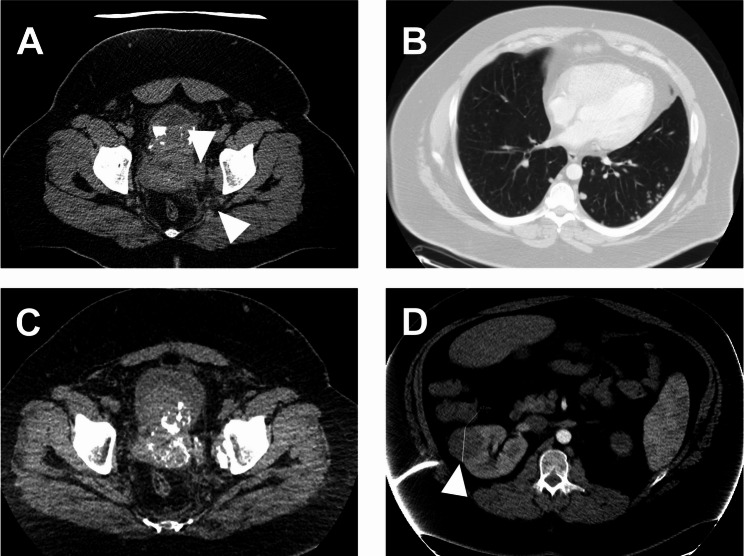

在这个病例报告中,我们描述了一例膀胱尤文样高级别小圆细胞肉瘤,其中发现了极其罕见的EWSR1::BEND2融合。一位28岁的男性患者以血尿表现,在随后的检查中发现了一个大的坏死性膀胱肿瘤,并扩散到邻近的前列腺组织和多发肺转移。组织学表现为低分化小圆细胞瘤,伴血管周围玫瑰花状组织,CD99中度膜性阳性。肿瘤的甲基化谱与肉瘤分类器分组的任何肿瘤实体都不匹配。随着肿瘤诊断方法,主要是下一代测序,新的融合正在加速被发现。我们的病例加入了不断扩大的EWSR1融合肿瘤组,并描述了尤因肉瘤治疗方案对这种类型肉瘤的影响。随着在表现出不同临床行为和形态的肿瘤中检测到EWSR1重排,荧光原位杂交检测Ewing肉瘤的传统方法的相关性正在下降。将这些肿瘤分类为世卫组织定义的实体以指导治疗是一项挑战。

In this case report we describe a Ewing-like high grade small round cell sarcoma of the urinary bladder in which an extremely rare EWSR1::BEND2 fusion was found. A 28-year-old male patient presented with hematuria and in the following examinations a large necrotic bladder tumor with spreading to adjacent prostatic tissue and multiple lung metastases were found. Histology showed a poorly differentiated small round cell tumor with perivascular rosettes and moderate membranous positivity for CD99. The methylation profile of the tumor did not match with any of the tumor entities grouped by the sarcoma classifier. With tumor agnostic methods, mainly next generation sequencing, novel fusions are being found at an accelerating rate. Our case adds to the expanding group of EWSR1 fusion neoplasms, and describes the effects of a Ewing sarcoma treatment protocol on this type of sarcoma. The relevance of traditional methods for detecting Ewing sarcoma with fluorescence in situ hybridization is decreasing as EWSR1 rearrangements are detected in tumors that show different clinical behavior and morphology. The classification of these tumors into WHO defined entities to guide treatment is a challenge.